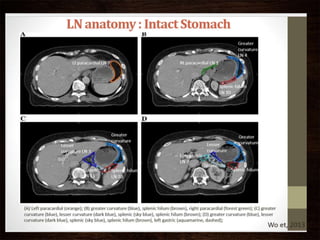

LYMPH NODE RESECTION

• D0 – incomplete removal of LN along lesser & greater curvature.

• D1 – gastrectomy as applicable

+ rt/lt cardiac LNs + lesser & greater curvature + supra & infra pyloric

• D2 – D1 + celiac trunk along with its 3 arteries (left gastric, common

hepatic, splenic artery.) + splenic hilum.

• D3- D2 + hepatoduodenal ligament +superior mesenteric vein &

retropancreatic

LYMPH NODE RESECTION •D0 – incomplete removal of LN along lesser & greater curvature. • D1 – gastrectomy as applicable + rt/lt cardiac LNs + lesser & greater curvature + supra & infra pyloric • D2 – D1 + celiac trunk along with its 3 arteries (left gastric, common hepatic, splenic artery.) + splenic hilum. • D3- D2 + hepatoduodenal ligament +superior mesenteric vein & retropancreatic